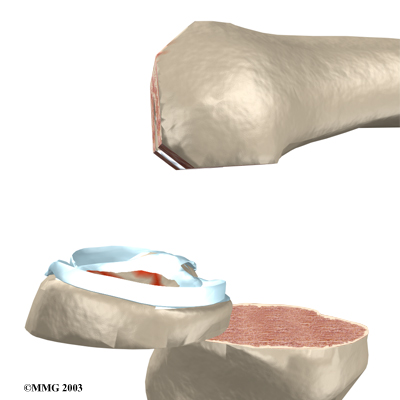

Next, the surface of the tibia is prepared.

Another type of cutting guide is used to cut the tibia in the correct alignment.

Then the artificial surface of the patella is removed.

The metal tray that holds the plastic spacer is then attached to the top of the tibia. This metal tray is either cemented into place, or held with screws if the component is of the uncemented variety. The screws are primarily used to hold the tibial tray in place until bone grows into the porous coating. (The screws remain in place and are not removed.)

The plastic spacer is then attached to the metal tray of the tibial component. If this component should wear out while the rest of the artificial knee is sound, it can be replaced. The replacement procedure is called a retread.

View animation of inserting the tibial component: